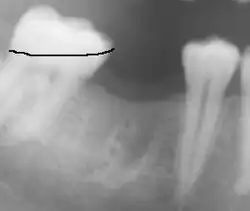

Prothetischer Zahnäquator. Nebenbefund: Die Knochenfächer des ersten Molaren sind nach der Zahnentfernung noch nicht gänzlich wieder verknöchert.